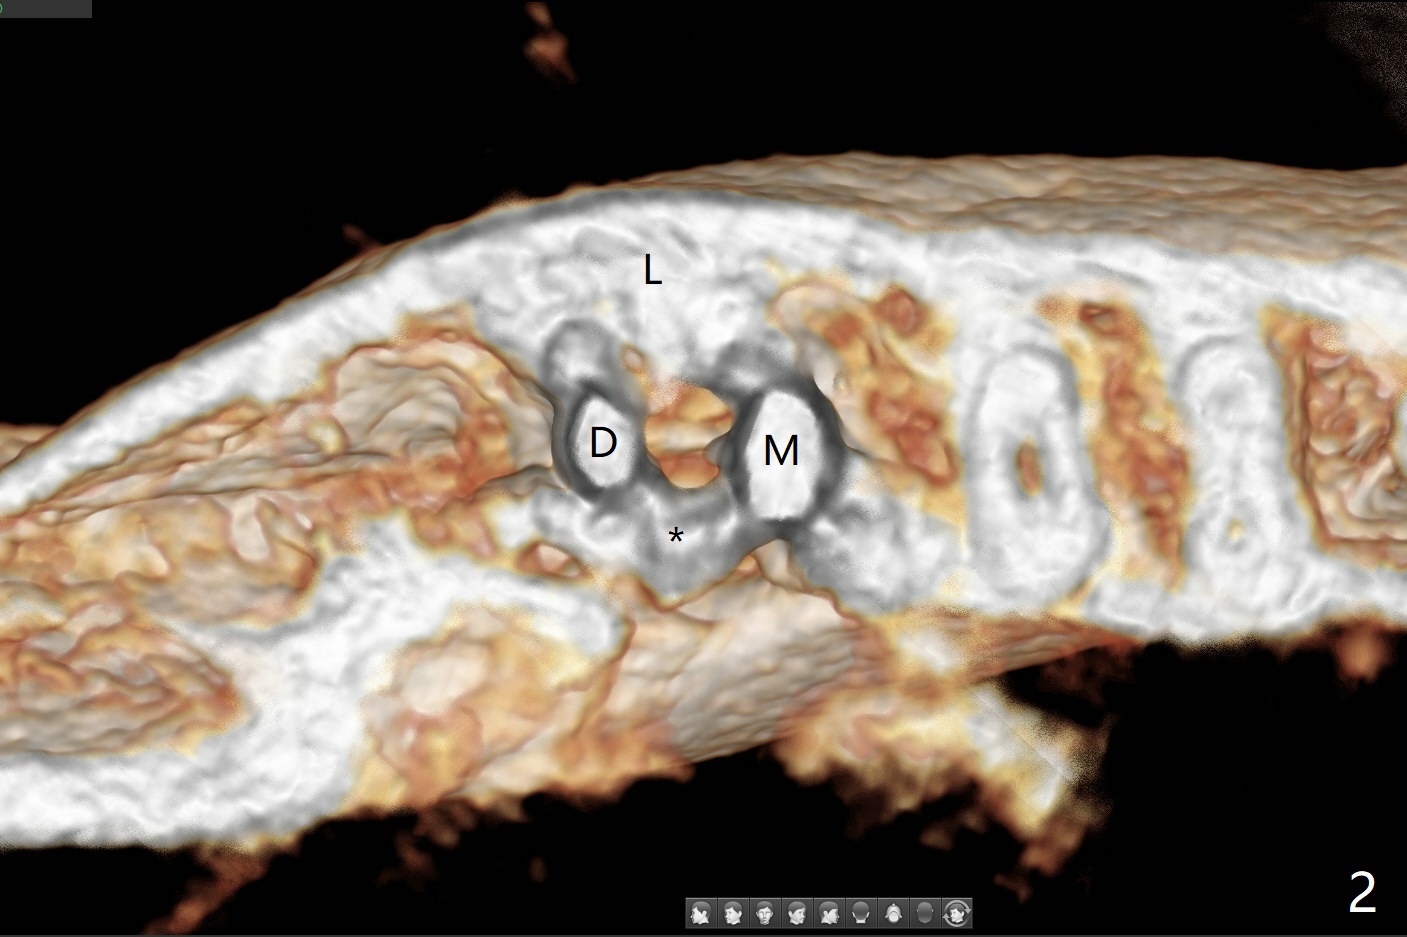

36岁女,右下第二磨牙颊侧瘘道,近中牙槽窝(图一:M)离下牙槽神经远,将是种植位点。图二是该牙CT3维横断面,显示近中(M),远中(D)牙根之间颊侧(L: 舌侧)连接(*);牙齿拔除后,牙槽窝成C型(图三,面对舌侧);由于颊侧骨板(图四:B)中断,缺损,植体将植入近中舌侧牙槽窝(绿色,导板)。优点便是三面骨质包绕(rao,图五),只有颊侧需要大量粘性骨粉(图六:*)。